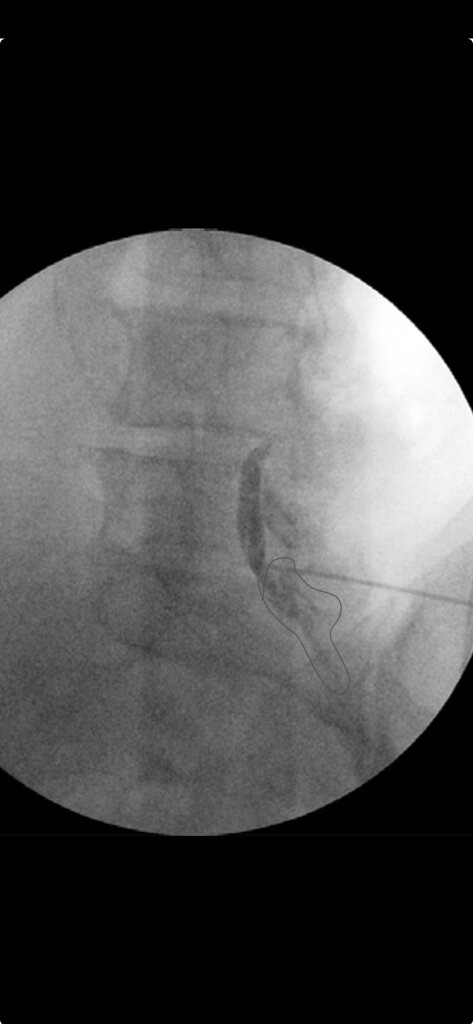

Hi all. I came across this picture during a review and the authors labeled this image as not epidural. I wanted to get folks thoughts on this. I admit I'm still a relatively new staff so If this looks this is blatantly not an epidural pattern I am happy to take pointers and learn. I feel fairly confident in identifying patterns that look classic like textbook images but sometimes for whatever reason (bad spines, volume of contrast used, could be technique too) I get patterns that don't look classic for epidural, subdural or otherwise. In fellowship for some reason they usually looked fairly obvious. I feel uncomfortable with these "in between" looking patterns and was wondering if people have shots of non-textbook looking epidural flows that are still epidural or tricky to identify patterns. All of the articles I find have pretty classic shots but none have in between. Even my colleagues who have 10 and 20+ years of experience disagree on some flows patterns when I ask them.

I think I see fat blebs

Looks epidural.

Looks like the pattern you’ll get if you’re a few degrees off plane from the lamina in CLO.

A lot of this contrast looks like it is not epidural. This looks like ipsilateral oblique and not CLO. I cannot identify a SP. The only VILL I can make out is on the other side of the spine. The area circled above looks like contrast behind the spine, running down the lamina. This is a poorly documented procedure without additional images.

That circled area is anterior to S1 lamina. Tips of footballs marked. VILL clearly defined by posterior margin of contrast. Classic CLO spread.

Clearly epidural, with contrast covering inferior L4 to S2. That pt could have been decompressed at L4, have a little scoliosis or a million reasons why the pic isn’t perfect, but it’s still epidural.

Looks epidural with the top spread (beneath lamina, not moving into subdural space)

It's by a well-known Pysiatrist. He points to the CLO image as an example of a "subdural with cystic flow" I've never heard of that. It's reassuring to know that this CLO looks epidural or posterior to the epidural space to most of us. I was beginning to question my training. Lol.

Just to add my 2cents, late to the game of course, is that the original picture is fishy and not clear epidural spread. It's too far obliqued and poor resolution to see the layers properly. The contrast also looks too "thick" from my experience. I usually see a very thin line. I would be concerned it's not epidural. Of course, I would look at other views to confirm. After seeing the AP posted later, I would say no to epidural spread. It's far too thick/dense midline to be epidural. I don't usually take true laterals unless I feel I'm losing the needle tip in the contrast on my approach.